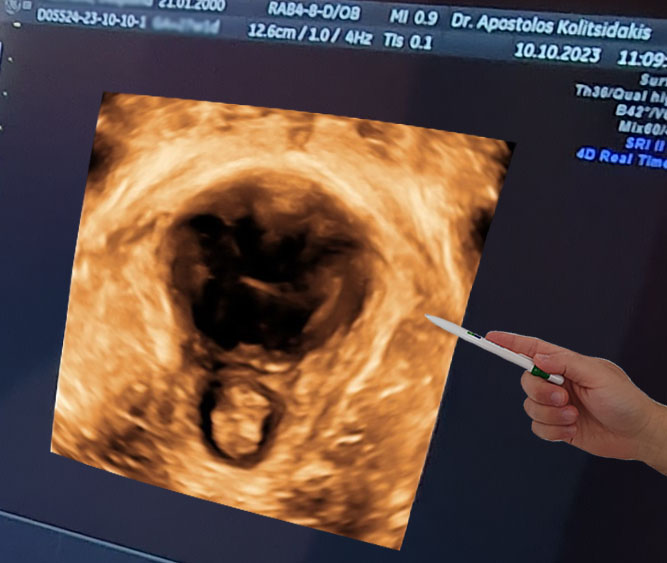

Υπέρηχος GE Voluson E8

Η εταιρεία GE θεωρείται η κορυφαία στον κόσμο των υπερήχων. Ο τίτλος Ε8 ανήκει στα μηχανήματα ύψιστης ευκρίνειας που χρησιμοποιούνται αποκλειστικά στα μεγαλύτερα κέντρα υπερήχων διεθνώς.

3D και 4D πυελικό υπερηχογράφημα